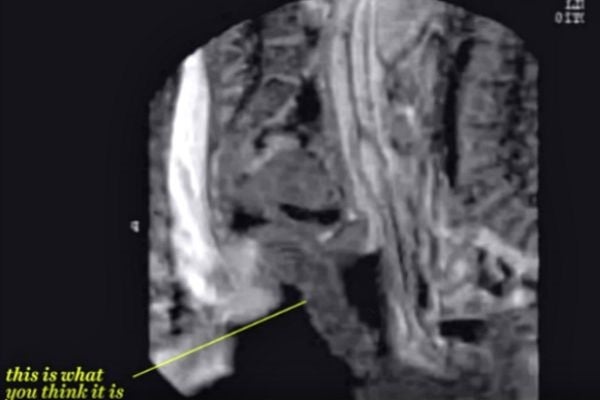

3. No, your eyes aren't deceiving you.

Yep, put that on your list of "things I never thought I'd see, and probably never want to see again."

4. When a man and a woman love each other, they sometimes make a baby.

The MRI machine also captured a baby in utero. It's pretty amazing how much detail you can see on the baby — fingers, toes, eyes, and brain.